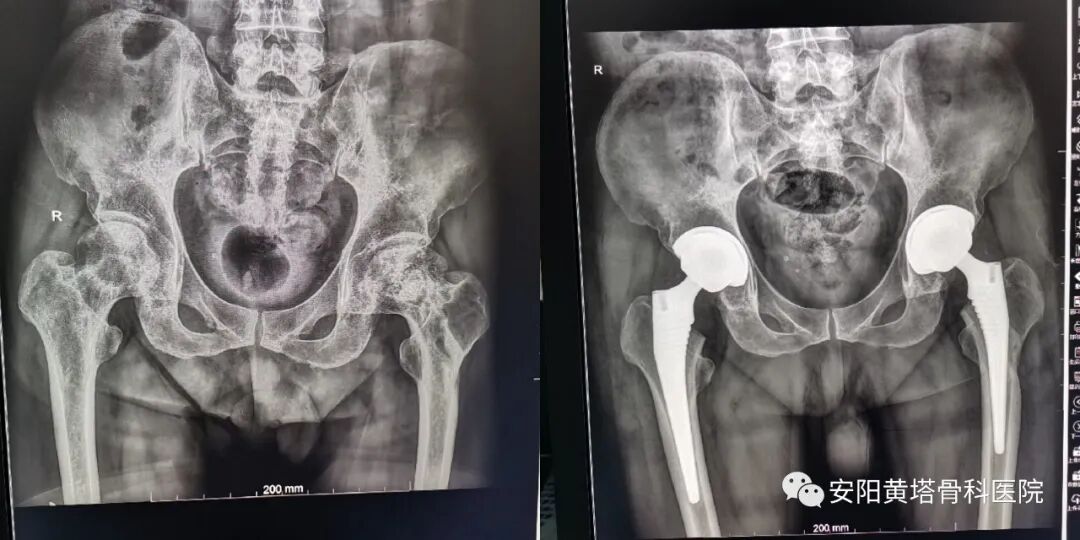

王东方    骨科二病区

副主任医师,原解放军*五一医院骨科主任。擅长髋、膝、肩关节置换及颈、腰椎间盘突出的手术治疗,尤其腰间盘突出微创治疗后创伤小、复发率低。微创治疗各种创伤骨折愈合率高,对颈肩腰腿痛及各种疼痛性疾病有独特的微创治疗手段。

髋关节置换

图片